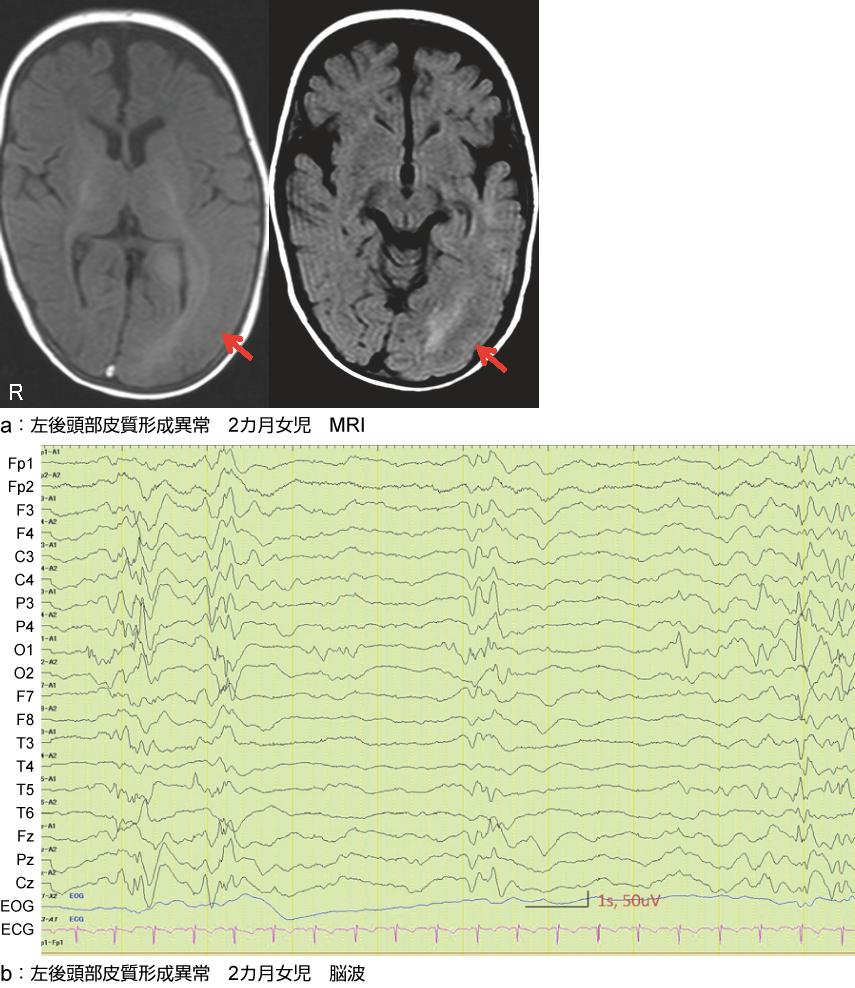

皮質形成異常:2カ月女児のMRI、脳波

左後頭部に皮質形成異常(矢印)を認める。左後頭部優位のspike、suppression-burst様の変化を認める。短い強直発作、眼球偏位はバルプロ酸、クロバザム、ビタミンB6で消失、脳波も改善した。

a:左後頭部皮質形成異常 2カ月女児 MRI

b:左後頭部皮質形成異常 2カ月女児 脳波